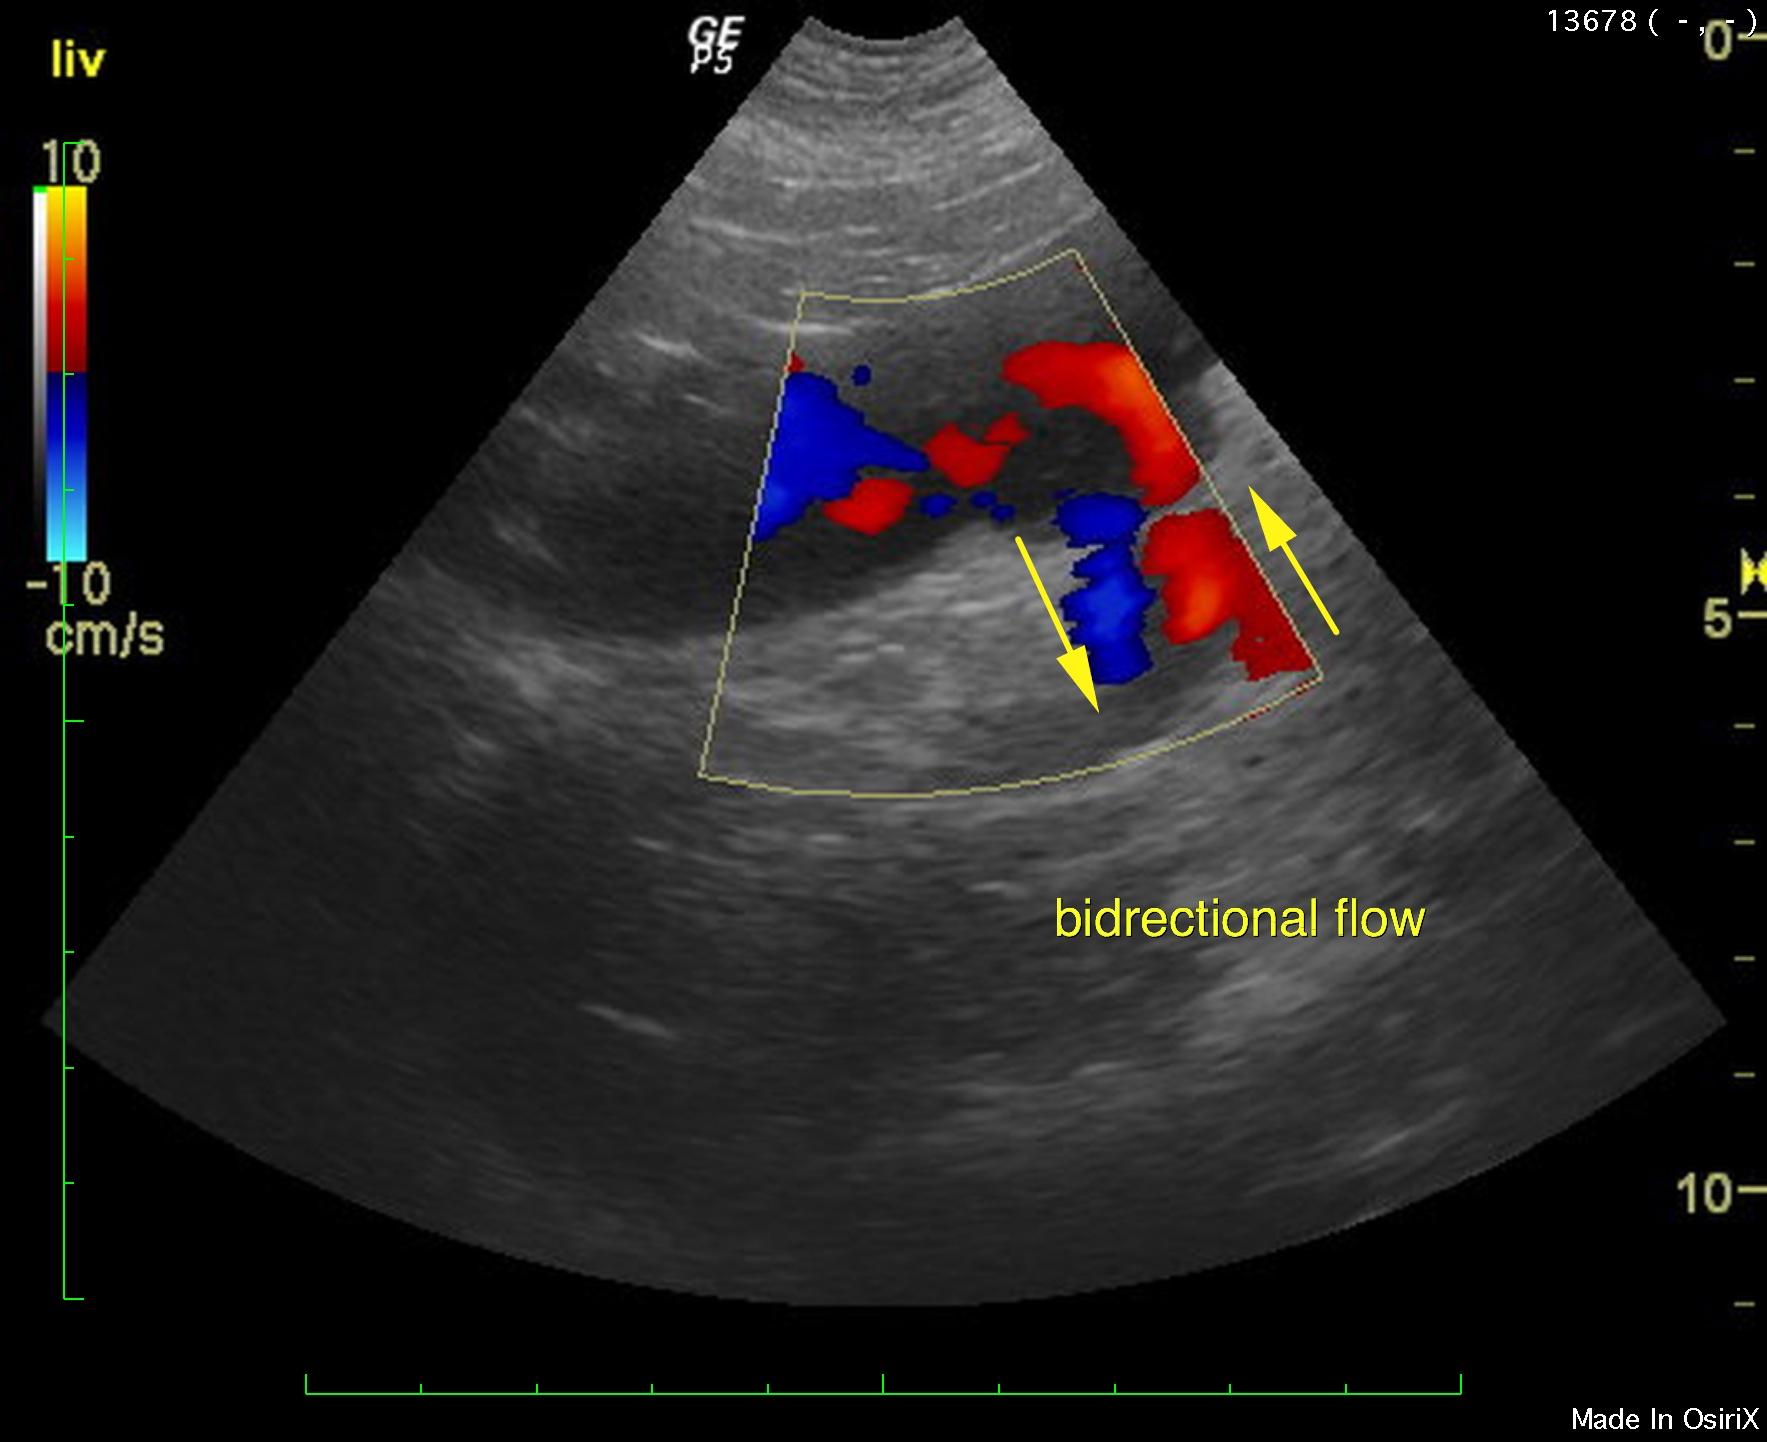

An 11-year-old FS Cane Corso dog was presented post ovariohysterectomy for evaluation of anorexia and an incision site painful seroma that was dripping serosanguinous fluid. Fluid cytology showed the presence of neutrophils.